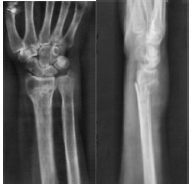

ճաճաևչոսկրի դիստալ Մետաէպիֆիզի տեղաշարժված կոտրվածք

Կոևտրոլ`դիաֆիքսացիայից հետո